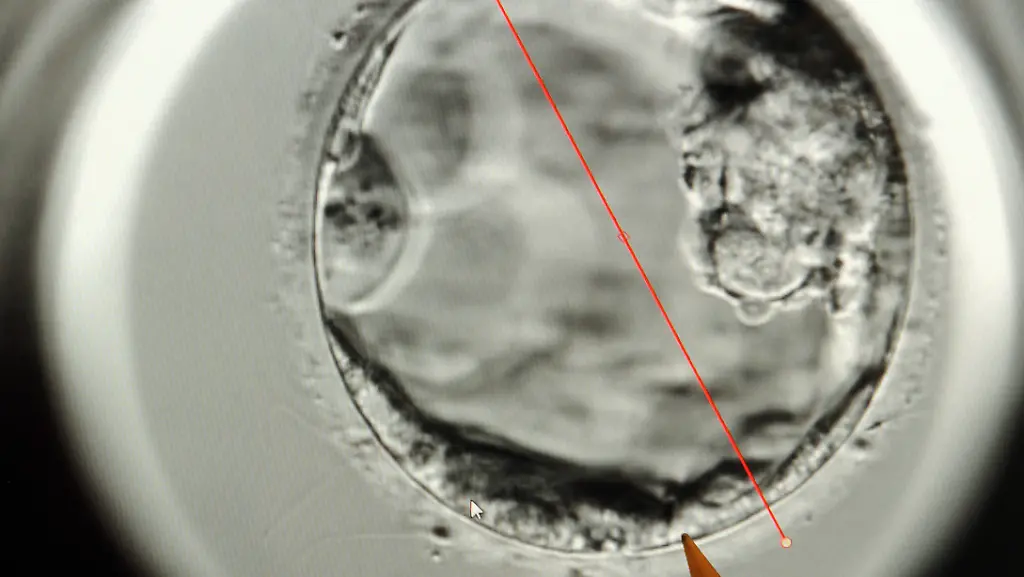

Befruchtete Eizellen nisten sich etwa am Tag sieben ihrer Entwicklung als kugeliger Zellhaufen in der Gebärmutterschleimhaut ein. Anschließend spezialisieren sich die Zellen. Aus einigen geht der Embryo selbst hervor, aus anderen die Plazenta, die seine Ernährung in der Schwangerschaft sicherstellt. "Dieser Teil der menschlichen Entwicklung war eine völlige Black-Box", berichten die Forscher um Ali Brivanlou von der Rockefeller University in New York, der das erste Team geleitet hat.

Um die Abläufe besser zu untersuchen, nutzten sie eine Technik, die Magdalena Zernicka-Goetz von der University of Cambridge, Leiterin der zweiten Forschergruppe, zuvor an Mäusen etabliert hatte. Dabei kultivieren die Wissenschaftler die Embryonen mit Hilfe einer optimierten Nährlösung und stellen ihnen ein Gerüst bereit, an dem sie sich anheften können. Durch chemische Markierungen verschiedener Zelltypen in dem Embryo verfolgten die Wissenschaftler dessen Entwicklung. Sie wurden so Zeuge, wie sich der Epiblast - jene Zellen, aus denen im Verlauf der Schwangerschaft das komplette Kind entsteht - von den beiden Zell-Linien trennt, aus denen die Plazenta und der Dottersack hervorgehen.

Die Studien legten die Grundlage für ein besseres Verständnis der embryonalen Entwicklung über die Einnistung hinaus, schreibt Janet Rossant vom Hospital for Sick Children in Toronto (Kanada) in einem erläuternden Kommentar zu den Studien. Mit ihrer größtenteils abgeflachten und zwei-dimensionalen Gestalt seien die kultivierten Embryonen aber eindeutig keine perfekten Modelle der normalen dreidimensionalen embryonalen Entwicklung.